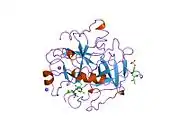

Structure

The molecular weight of prothrombin is approximately 72,000 Da. The catalytic domain is released from prothrombin fragment 1.2 to create the active enzyme thrombin, which has a molecular weight of 36,000 Da. Structurally, it is a member of the large PA clan of proteases.

Prothrombin is composed of four domains; an N-terminal Gla domain, two kringle domains and a C-terminal trypsin-like serine protease domain. Factor Xa with factor V as a cofactor leads to cleavage of the Gla and two Kringle domains (forming together a fragment called fragment 1.2) and leave thrombin, consisting solely of the serine protease domain.[17]

As is the case for all serine proteases, prothrombin is converted to active thrombin by proteolysis of an internal peptide bond, exposing a new N-terminal Ile-NH3. The historic model of activation of serine proteases involves insertion of this newly formed N-terminus of the heavy chain into the β-barrel promoting the correct conformation of the catalytic residues.[18] Contrary to crystal structures of active thrombin, hydrogen-deuterium exchange mass spectrometry studies indicate that this N-terminal Ile-NH3 does not become inserted into the β-barrel in the apo form of thrombin. However, binding of the active fragment of thrombomodulin appears to allosterically promote the active conformation of thrombin by inserting this N-terminal region.[19]